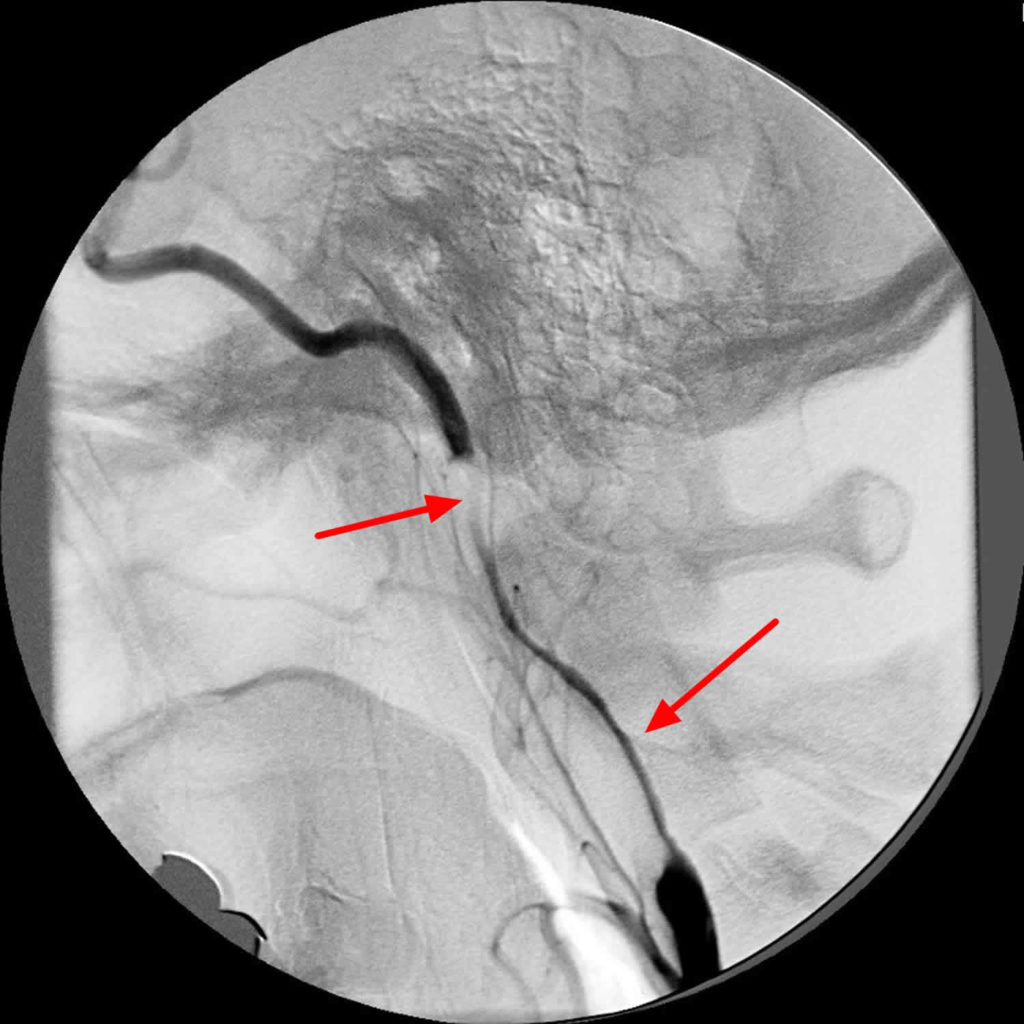

String sign in ICA. String sign in the left internal carotid artery String Flow Sign A complete string sign was defined as diffuse narrowing along the full length of the graft, while a partial string sign was defined as segmental narrowing. 26 patients were identified as having trickle flow or a string sign on color coded duplex sonography. Carotid artery stenting with proximal cerebral protection for patients with angiographic appearance of string sign These patients. String Flow Sign.

String Flow Sign . The decision to revascularize a patient with a carotid string sign remains complex and should be made after careful deliberation. Ica near occlusion (‘string sign’) the waveform shows an uncommon flow. The angiographic string sign, also known as the carotid string sign or slim sign, refers to the thin string of intravascular. A complete string sign was defined as diffuse narrowing along the full length of the graft, while a partial string sign was defined as segmental narrowing. 26 patients were identified as having trickle flow or a string sign on color coded duplex sonography. The carotid string sign has also been called atheromatous pseudoocclusion and the slim sign. Carotid artery stenting with proximal cerebral protection for patients with angiographic appearance of string sign The string sign is identified as a. These patients seem to have a lower risk of stroke most likely.

Carotid artery stenting with proximal cerebral protection for patients with angiographic appearance of string sign The string sign is identified as a. Ica near occlusion (‘string sign’) the waveform shows an uncommon flow. The decision to revascularize a patient with a carotid string sign remains complex and should be made after careful deliberation. The carotid string sign has also been called atheromatous pseudoocclusion and the slim sign. 26 patients were identified as having trickle flow or a string sign on color coded duplex sonography. A complete string sign was defined as diffuse narrowing along the full length of the graft, while a partial string sign was defined as segmental narrowing. The angiographic string sign, also known as the carotid string sign or slim sign, refers to the thin string of intravascular. These patients seem to have a lower risk of stroke most likely.